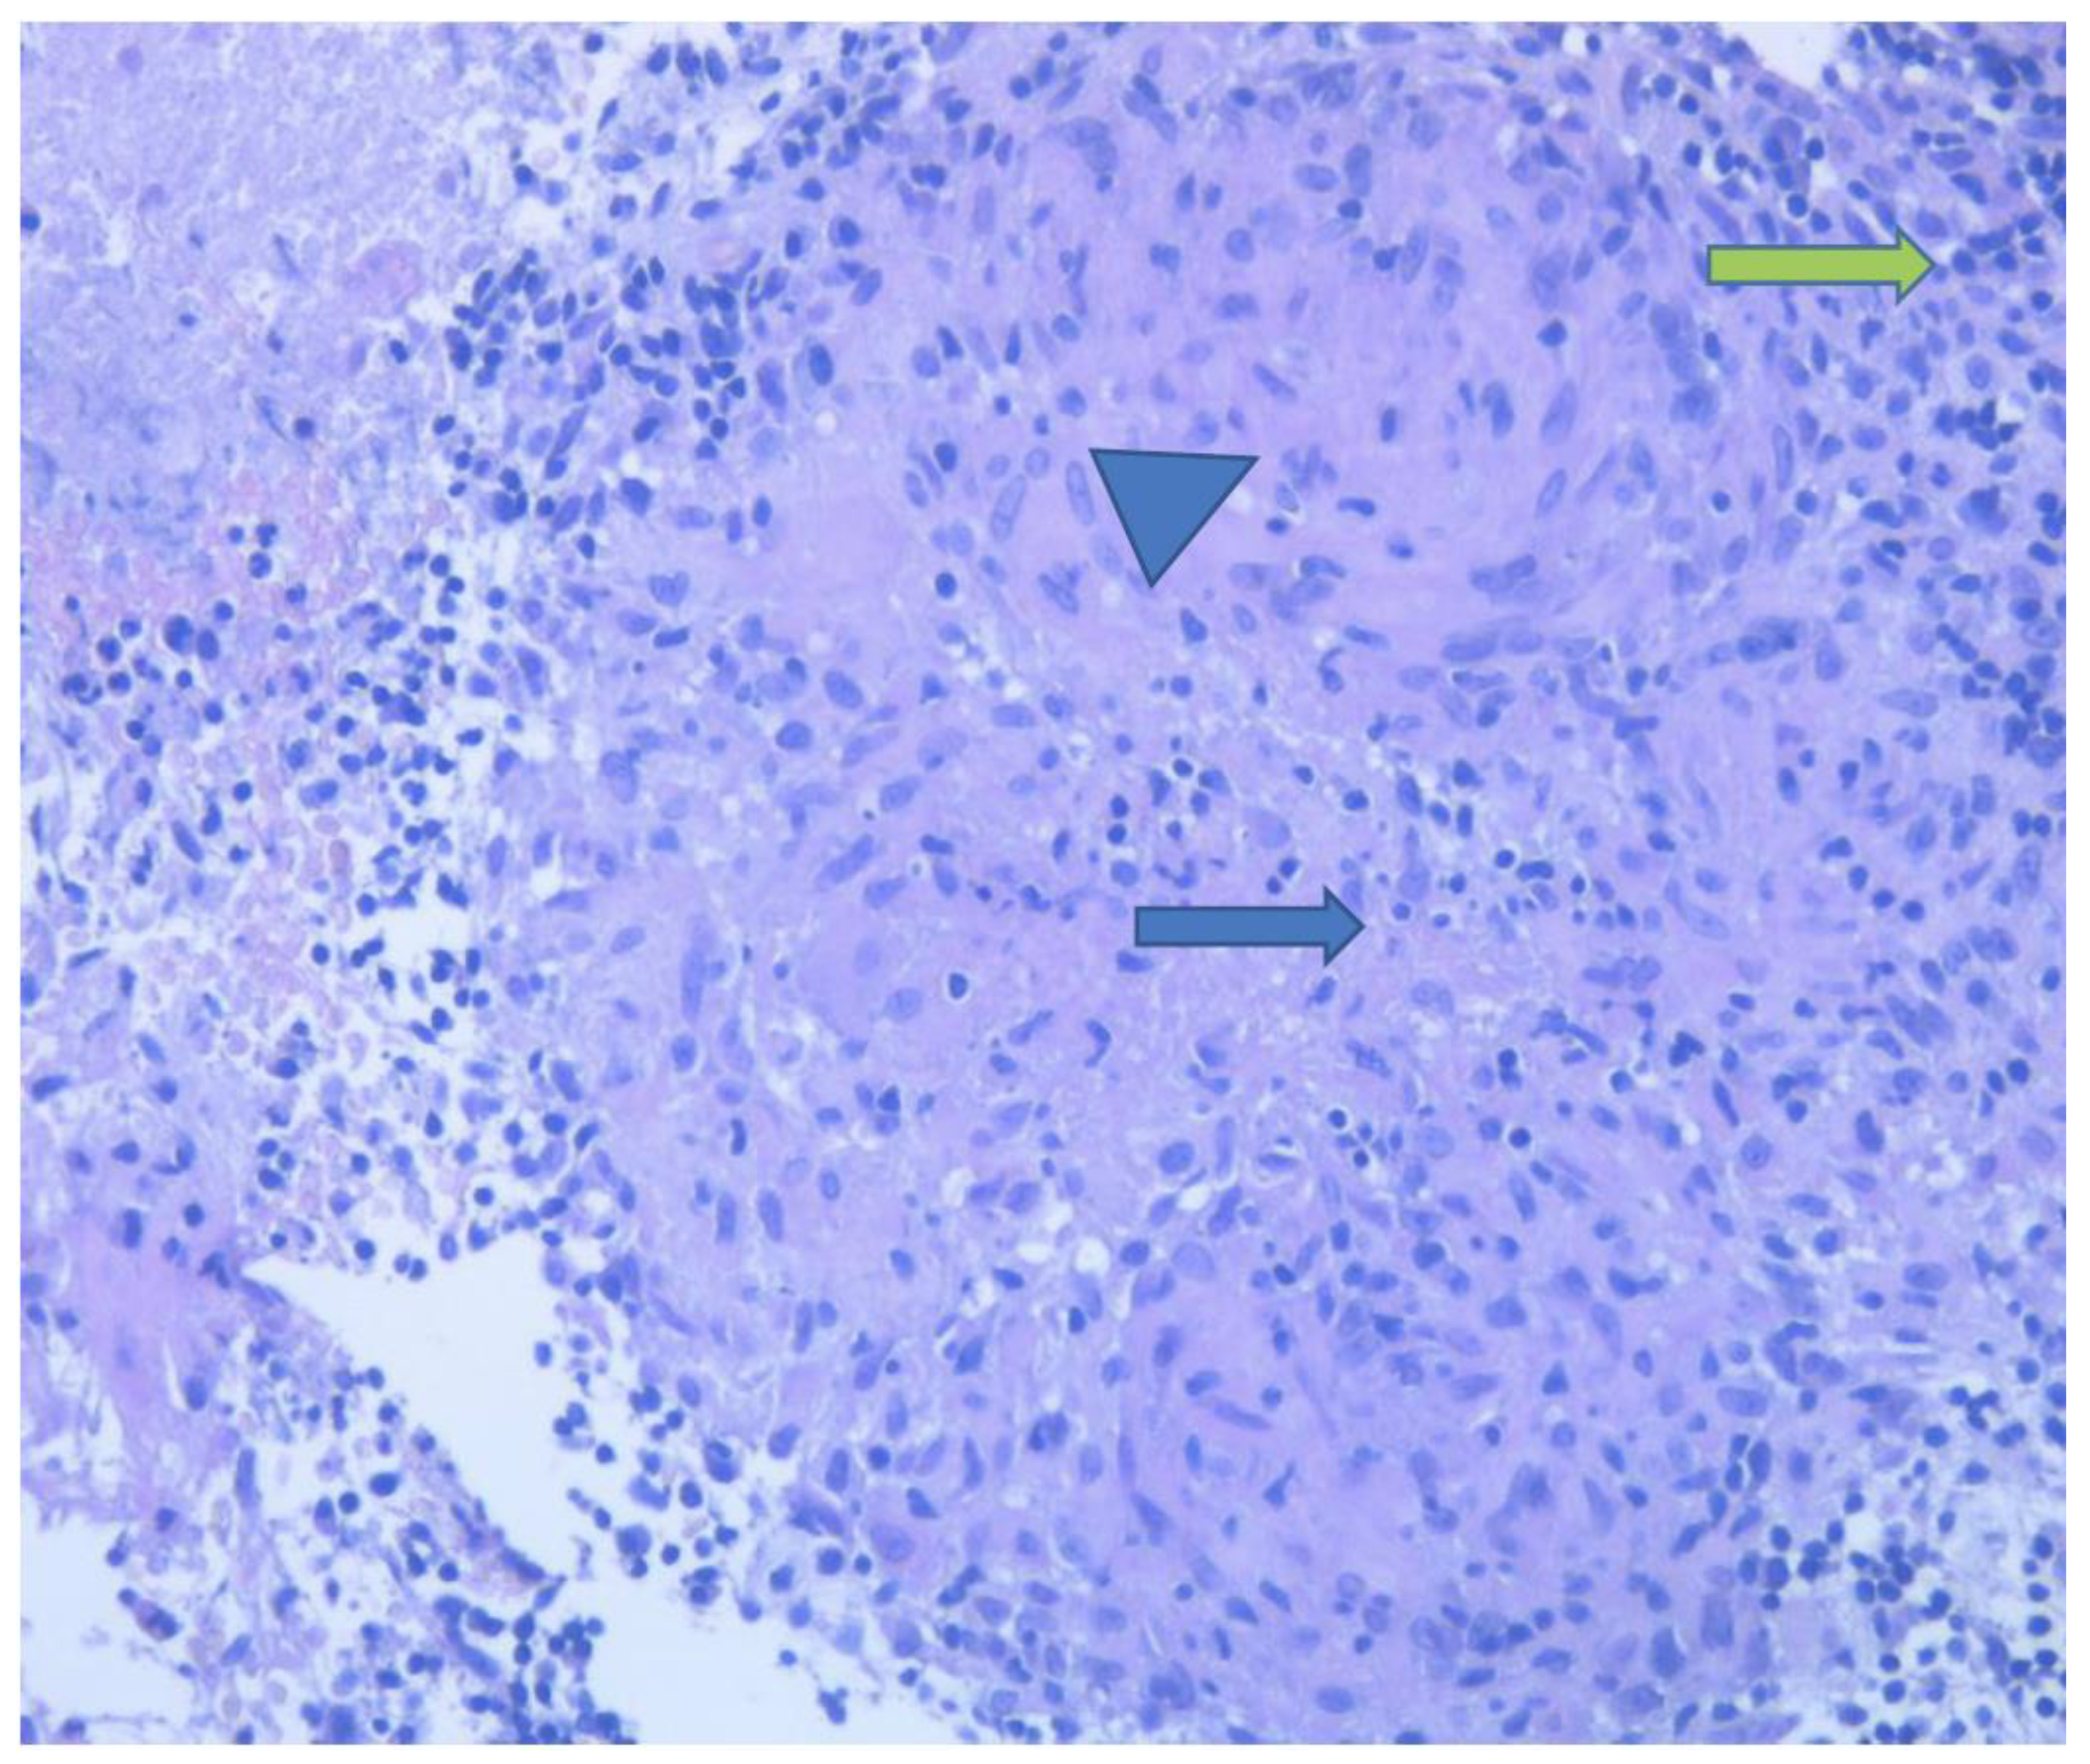

2. Detailed Case Presentation